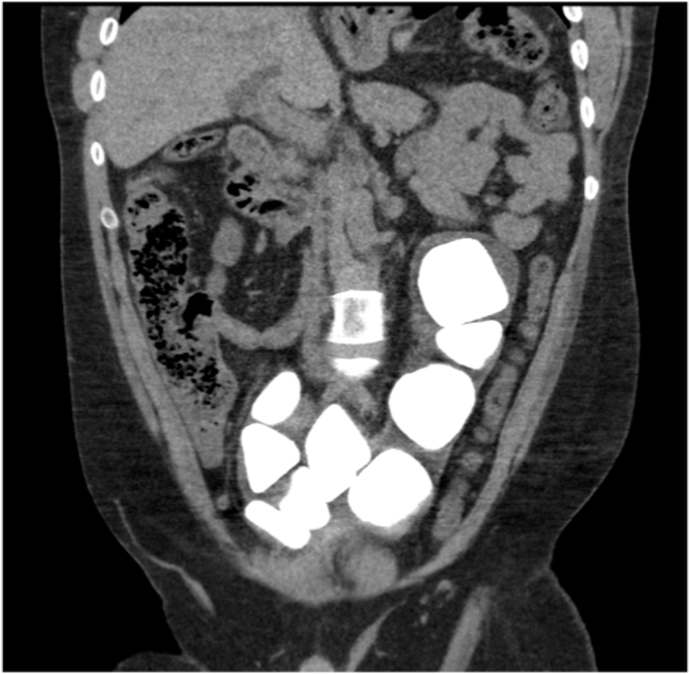

Unfortunately, the patient did not return for his operation and was unable to be contacted for follow-up. Five years later, his General Practitioner (GP) referred him back to our service with recurrent UTIs. His urine cultures showed mixed bacterial growth. A computed tomography (CT) scan showed enlarging bladder stones (Fig. 2) and he was booked again for an open cystolithotomy. After several further delays due to other commitments, he underwent the operation seven years after his initial x-ray.

Fig. 2.

Coronal slice from CT KUB demonstrating enlarged bladder stones in augmented bladder.